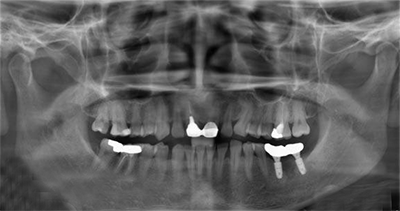

术前X-ray

术前X-ray局部放大图